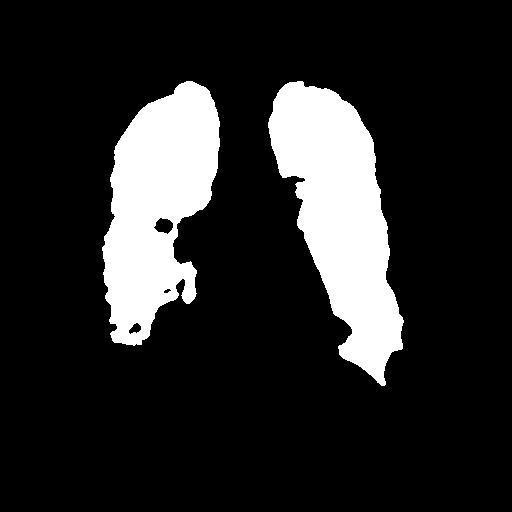

The dataset chosen in this paper is an open-source dataset, the dataset is selected from the open-source database, the database contains 150 lung X-ray images and their corresponding 150 masks, and we select four of them for presentation, the results are shown as follows, the four images in the first row are the original images of the lung X-ray, and the images in the second row in the corresponding position are their corresponding masks, as shown in Fig. 1.

Figure 1. Partial data.